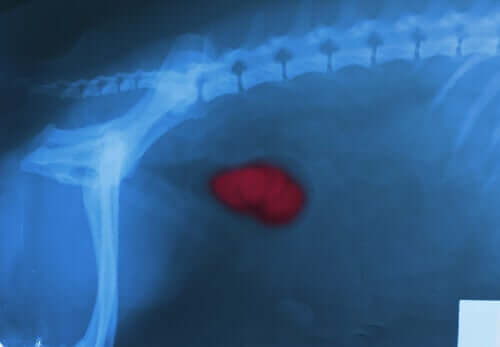

Neoplasias

As neoplasias, tanto benignas quanto malignas, são crescimentos anormais de massas em algum órgão ou tecido. A hiperplasia de próstata, o hemangioma e o angiossarcoma, por exemplo, costumam causar sangramento.